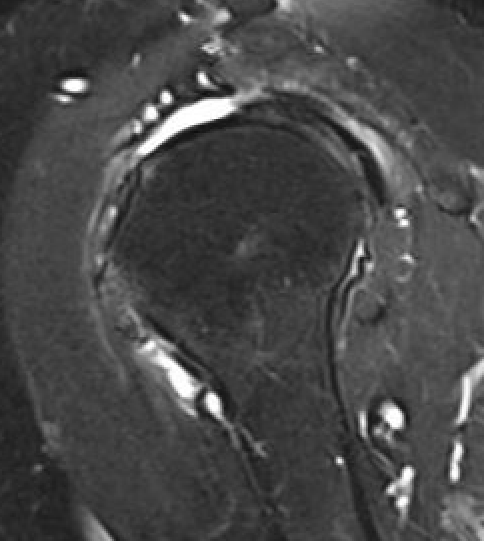

Full thickness rotator cuff tears

Partial bursal sided tear Partial articular sided tears

Subscapularis tears

Measure tear in the coronal and sagittal plane

Small full thickness rotator cuff tear of supraspinatus - retracted to footprint

Large full thickness tear of supraspinatus and infraspinatus tendon - retracted to midhumeral head

Massive rotator cuff tear of the supraspinatus and infraspinatus tendon - retracted to glenoid